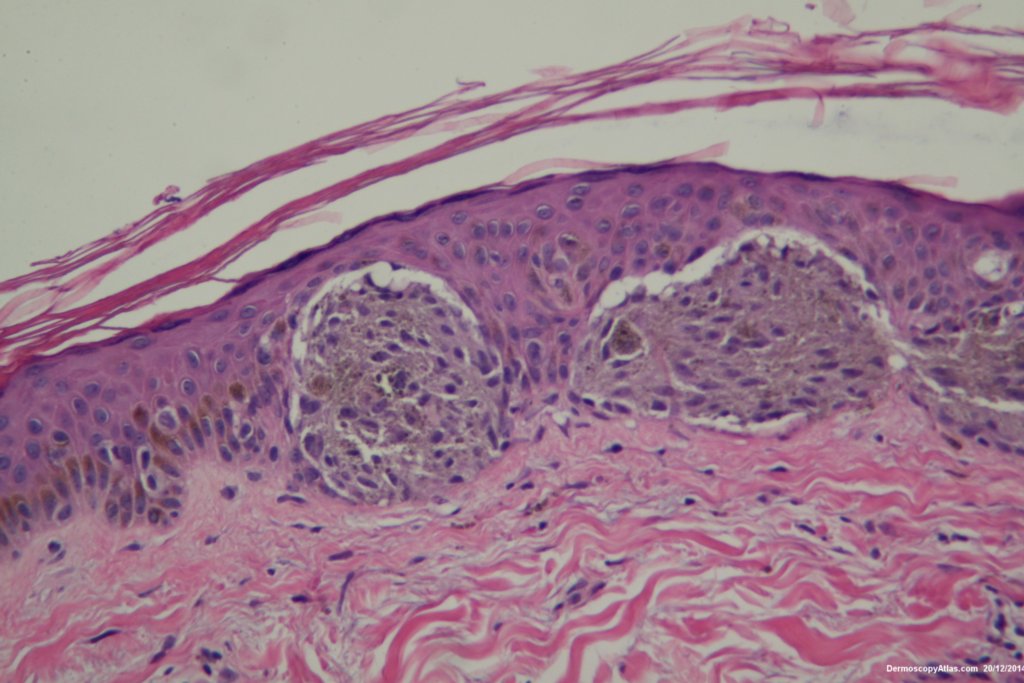

The histopathology shows nests of epitheliod and spindled cells with lots of melanin in them. There are a few melanophages in the dermis. There is no inflammatory reaction beneath this lesion. There were no mitoses. This is just a junctional lesion ie no nests of cells in the dermis.